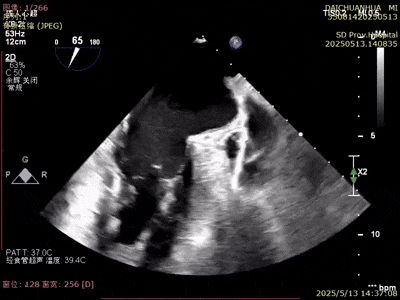

術(shù)前超聲

A3脫垂連枷(脫垂高度9mm,連枷高度:7mm),反流等級(jí)MR 4+(反流寬度11mm),有效瓣環(huán)面積MVA約6.3cm²。前瓣葉長(zhǎng)度23,后瓣葉長(zhǎng)度14.5mm,瓣環(huán)直徑AP 29mm。